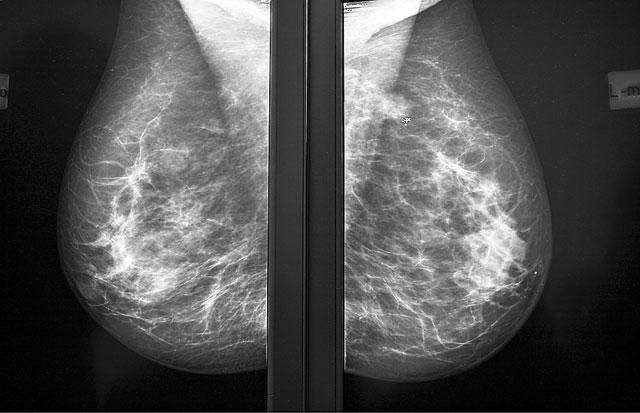

Не успел утихнуть разразившийся в США скандал, связанный с возможной отменой PSA-тестирования для выявления у мужчин рака простаты, как наметился новый, на этот раз в Великобритании. Теперь речь зашла о женщинах. В ближайшее время в этой стране могут измениться схемы профилактики рака груди. Эксперты уверяют, что маммография, которая используется для выявления злокачественных опухолей молочной железы на ранних стадиях, на самом деле принесла не так уж много пользы, а многим пациенткам просто исковеркала жизнь.

История началась с публичного вызова, брошенного Майку Ричардсу, директору национальной онкологической службы. В конце октября на сайте «Британского медицинского журнала»

появилось открытое письмо профессора медицины Лондонского королевского колледжа Сьюзан Бьюли. Взволнованная дама, в семье которой немало женщин пострадало от рака груди, обвинила чиновников Национальной службы здравоохранения Великобритании в том, что они скрывают правду о негативных последствиях маммологического скрининга, который, между прочим, обходится британским налогоплательщикам в 96 миллионов фунтов стерлингов ежегодно. Откуда информация об осложнениях? Из обзоров международного Кокрейновского сообщества — независимого объединения профессионалов, созданного для качественной оценки эффективности здравоохранения. Выкладки экспертов вошли в настоящий клинч с официальной точкой зрения. Судите сами. В 2002 году Международное агентство по онкологическим исследованиям при Всемирной организации здравоохранения объявило, что маммологический скрининг снижает смертность от рака груди в среднем на 35 процентов. Национальная служба здравоохранения Великобритании приводит не менее впечатляющую цифру — скрининг спасает в этой стране 1400 жизней в год. А вот кокрейновские эксперты говорят совсем другое. Они подсчитали, что каждая третья опухоль, выявленная при маммографии, не является смертельной или не способна расти. Значит, пациенток напрасно подвергают хирургическому вмешательству, химио- и лучевой терапии. По их данным, неправильный диагноз после маммографии в Великобритании ежегодно ставят 7 тысячам женщин. А в их обзоре клинических исследований говорится, что из каждых 2 тысяч пациенток, прошедших маммографический скрининг, лишь одной спасут жизнь. При этом 10 будут подвергнуты травмирующему лечению, в котором не нуждаются, а 200 столкнутся с серьезным многомесячным стрессом из-за ложных результатов, указывающих на рак...

Как в этой ситуации должна вести себя женщина, у которой нет факторов риска развития рака груди и которая не чувствует никаких признаков заболевания, но которую, как принято в Великобритании, приглашают регулярно, раз в три года, проходить маммографию после 50? Кому верить — одной группе экспертов или другой? Соглашаться на анализ или нет? Сьюзан Бьюли попросила главного британского онколога провести независимое расследование, чтобы покончить с беспочвенными утверждениями и попробовать обосновать хотя бы показатель в «1400 спасенных жизней». По ее словам, даже благотворительные фонды, которым на роду написано приукрашивать цифры, чтобы произвести впечатление на жертвователей, обычно оперируют более скромными оценками, чем медицинские чиновники. Майк Ричардс принял вызов и в таком же открытом письме в «Британском медицинском журнале» пригласил к сотрудничеству независимых экспертов. Он пообещал рассмотреть проблему непредвзято и подготовить новый обзор с учетом самых разных подходов и методик.

Результатов британского расследования с нетерпением ждут многие. Ведь это не первое наступление на программы маммографического скрининга, предпринятое в разных странах. В 2009 году Рабочая группа по профилактической медицине США предложила отменить скрининг у женщин от 40 до 49 лет, который до этого проводился ежегодно. Американские онкологи выступили против, подозревая, что государство хочет просто сэкономить на исследовании, в результате сошлись на том, чтобы проводить его раз в два года. Осенью этого года вновь заработавшая Канадская рабочая группа по профилактической медицине первой же директивой рекомендовала не проводить скрининг у женщин от 40 до 49 лет. После пятидесяти канадки будут теперь проходить скрининг раз в два-три года, а не каждый год, как раньше. Великобритания вроде бы и раньше не баловала своих пациенток чересчур частыми обследованиями, проводя их только после пятидесяти и раз в три года. Если теперь окажется, что и этого слишком много, под сомнение поставят саму идею — найти опухоль так рано, что ее еще нельзя прощупать, и начать бороться с ней, пока не появились метастазы. Что ни говори, а именно этот подход вкупе с современными методами лечения позволяет неуклонно снижать смертность от рака груди в развитых странах — примерно на 2,2 процента в год. Недавно специалисты объявили, что этот вид рака, обнаруженный на ранних доклинических стадиях, излечим практически на 100 процентов...